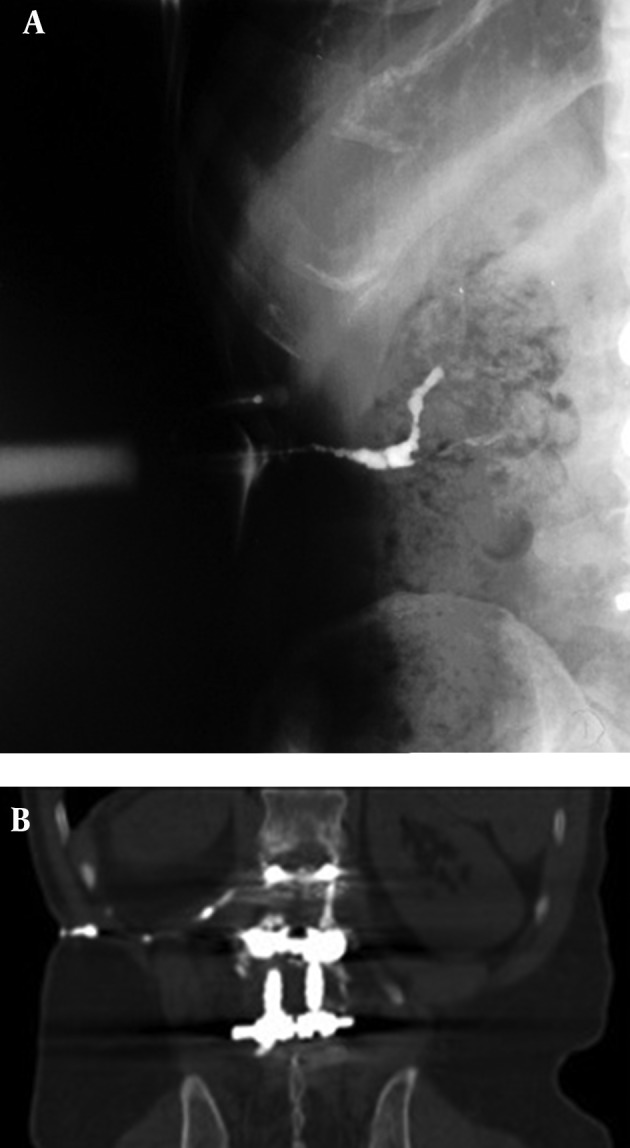

Introduction: A late-developing infection after an uneventful initial spinal instrumentation procedure is rare. Delayed infection and new fistula formation have been reported from a few months to 13 years. Here we report an unusual 17-year-delayed fistula formation after primary spinal instrumentation. The patient underwent hardware removal surgery with antibiotic therapy as a definitive treatment.

Case presentation: Here we report an unusual 17-year delayed fistula formation after primary spinal instrumentation due to spinal trauma. He was admitted to Ghaem General Hospital, a chief referral center, Mashhad, North-East of Iran in August 2014. The patient underwent hardware removal surgery with antibiotic therapy as a definitive treatment.

Conclusions: Late inflammation may occur around spinal instruments and results in cutaneous fistula formation. After oral or intravenous antibiotic treatment, total device extraction is the cornerstone of treatment.